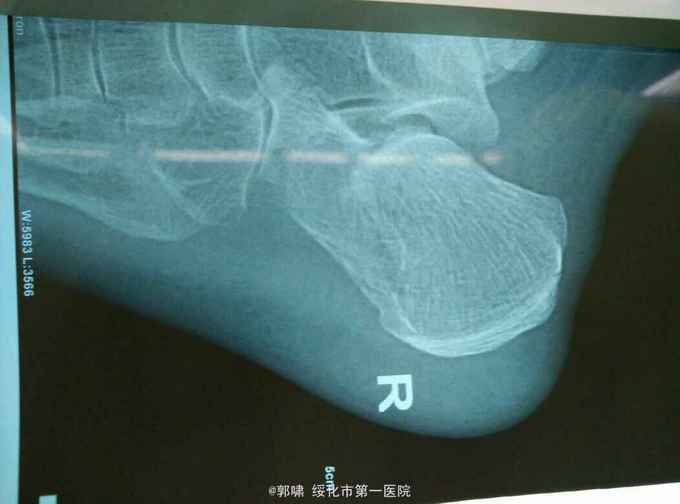

患者老年男性。76岁。自三米高处坠地。右侧跟骨肿胀痛,畸形,活动受限一小时。收入院。病人一小时前不慎自三米高处跌下,当即右足跟局部肿胀,疼痛,畸形。不能行走。立即来诊,门诊拍片示。右侧跟骨粉碎性骨折。收入院。

右侧足跟局部肿胀。足弓消失。局部皮下淤血。压痛。活动受限。不能行走。拍片示。右侧跟骨粉碎性骨折。

诊断。右跟骨粉碎性骨折。病人入院后常规检查。急诊腰麻下闭合复位。横向挤压恢复跟骨横径。克氏针撬拨恢复跟骨贝雷氏角。恢复跟骨关节面平整。沿跟骨长轴交叉传入细克氏针。拧入空心钉。